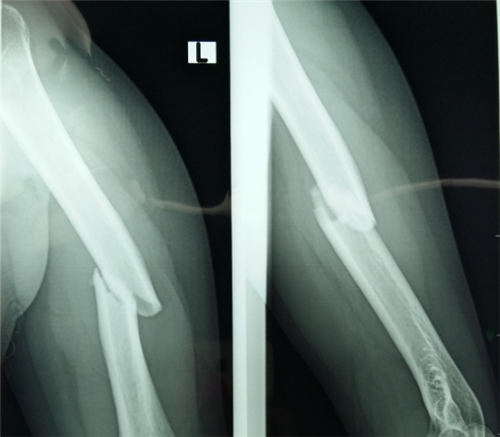

7、骨质疏松是小病:骨质疏松不只是腰酸腿痛,一旦发生脆性骨折,尤其是老年患者易发生髋部骨折,导致长期卧床,死亡率极高。